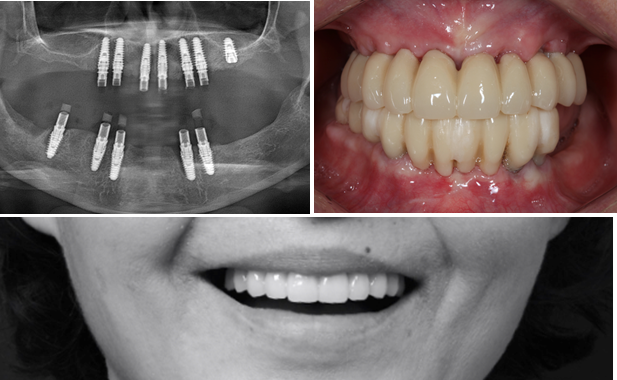

Effective R2STUDIO in complex tooth positioning

- Courtesy of Dr. Jong Cheol Kim, Korea